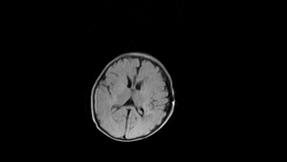

标题: PED3413:患儿女6天体检

缺血缺氧性脑病

6天为新生儿,髓鞘发育正常;左侧颞顶叶蛛网膜下腔增宽,请结合临床。

1。缺血缺氧性脑病2。左侧颞顶叶外部性脑积水,可观察

半卵圆中心上方层上可见对和乐大脑皮质t1高信号,考虑有hie可能,不知有何症状,建议加做dwi及复查

符合缺氧缺血性脑病影像表现。